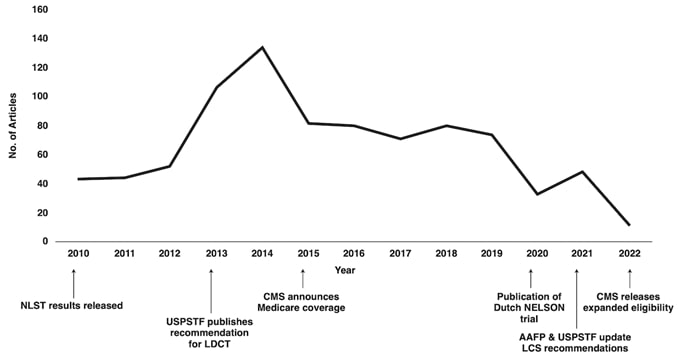

At the individual level, some of the barriers to awareness include unfamiliarity with LCS as a health preventive service tool (Fig. 2), unawareness of the new USPSTF and Centers for Medicare & Medicaid Services (CMS) recommendations for LCS, unfamiliarity with insurance coverage and costs, uncertainty about available accredited LCS programs, lack of culturally appropriate information, and lack of information at an appropriate health literacy level [8–10].

At the community and health care system level, suboptimal quality of institutional information about LCS (i.e., information not tailored for the surrounding communities) and a lack of institutional social media presence or engagement through social media campaigns to disseminate information about LCS are barriers to LCS [12, 13]. Furthermore, electronic medical records (EMRs) that are not optimized to automatically notify providers of eligible patients have been reported as a barrier [10].

At the individual level, facilitators for LCS are creating patient-centered, culturally tailored educational content to increase interventions to raise awareness and increase health literacy about the new guidelines and fostering non-stigmatizing language and guidelines from national organizations such as the International Association for the Study of Lung Cancer (IASLC) [4, 10, 12, 14]. An effort must be made to inform patients about the importance of early LC detection through LCS, the availability of insurance coverage, and the location of nearby LCS centers using websites such as the “Lung Cancer Screening Locator Tool” [10, 15]. Community health fairs, conventional media, social media, educational brochures, and mailed invitations are examples of how LCS educational information can be disseminated in multiple settings [10]. The educational material can be tailored to focus on hope based on the advancements in LC treatment by including patient testimonials about their experiences with LCS and by tailoring the education to fit the needs and capacities of diverse populations [10, 16]. Online content can provide information and details about LCS programs in multiple languages at the recommended health literacy levels [13]. The Internet and the use of social media can play a key role in the dissemination of information regarding LCS [17]. Prior studies have shown that digital awareness strategies leveraging social media were effective in increasing LCS engagement [17].

At the community and health care system level, an important facilitator to LCS is updating EMR systems to identify patients who are eligible for LCS under the new guidelines. This information can be incorporated into EMR systems with alerts for eligible high-risk patients, autopopulated referral tools, and lists of certified LCS centers that will help identify eligible patients and promote uptake among diverse patient populations [10, 22]. Online content can facilitate LCS by providing information about LCS programs that is tailored for the local communities served by radiology practices and health care institutions [10, 12]. Furthermore, implementing institutional social media campaigns that emphasize the expanded new eligibility criteria will help overcome knowledge gaps and barriers to awareness [23].